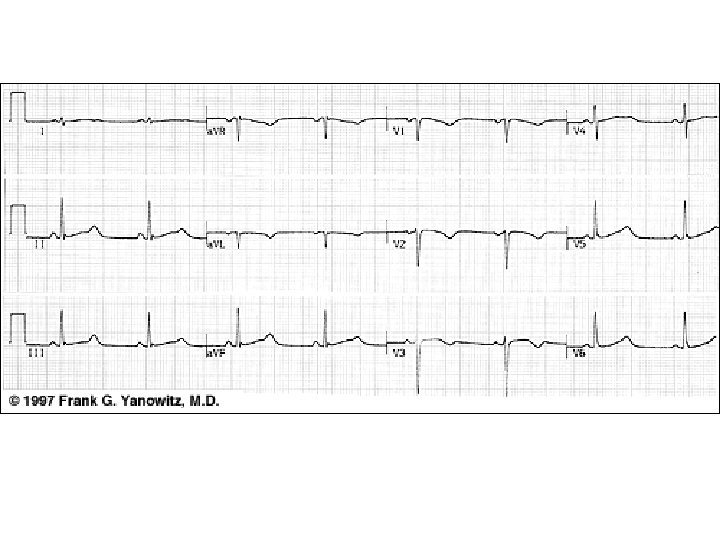

n Epsilon wave

Arrhythmogenic right ventricular dysplasia Deep T wave inversions in V 2 to V 4, compatible with right ventricular disease, and epsilon waves just after the QRS complex (arrows).

Case III • A 32 -year-old male is referred to you by his primary care provider after an episode of syncope. The patient was briskly walking with friends when he suddenly passed out with recovery after falling to the ground. The patient takes no medication and does not use illicit drugs. • A family history is notable for a father who died suddenly while shoveling snow at the age of 45. The physical examination is consistent with a healthy male with no distinct abnormalities. • His ECG is displayed on the next page. • An echocardiogram shows mild-to-moderate RV enlargement with a mild reduction in systolic function

Case III

Case III • The history, examination, and tests are most suggestive of what disease process? a. Arrhythmogenic RV dysplasia b. RVOT tachycardia c. HCM d. Long QT syndrome e. Vasovagal syncope